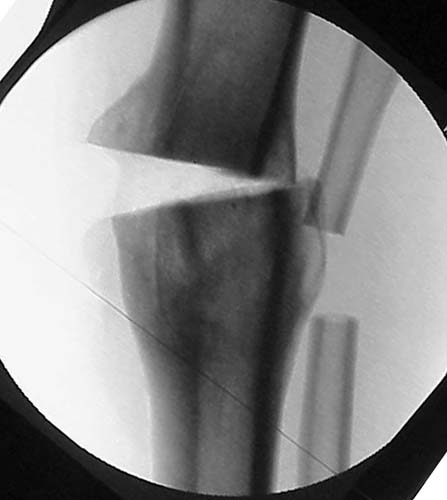

Thanks for the input on the tibia malunion w/ multiple plane deformity. I decided on a single cut osteotomy and IMN fixation based on desire to walk early, return to professor duties, and my previous experience w/ similar deformities (see another tibial malunion -below). The opening wedge was packed w/ a combination of autograft, allograft and demineralized bone.

Another tibial malunion -

Pt was 10 yrs s/p open tibia fx treated in a cast w/ IR, varus, 2 cm short, and recurvatum. He has done well post op.

preop

intraop

18 mos postop